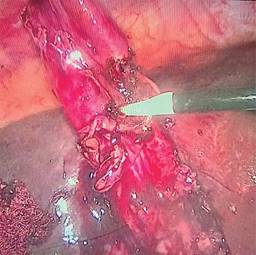

1. Efectuar una disección retrógrada de la vesícula biliar del fondo y del cuerpo lo más cercano a la porción infundibular (Figura 1).

2. Realizar sección transversa de toda la circunferencia de la vesícula biliar para evacuar su contenido e identificar el conducto cístico desde el interior de la vesícula (Figura 2).